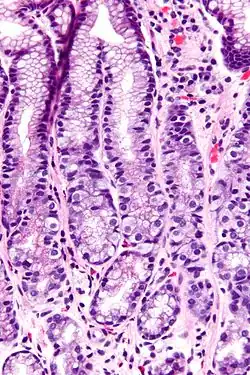

G cells have a distinctive microscopic appearance that allows one to separate them from other cells in the gastric antrum; their nuclei are centrally located in the cell. They are found in the middle portion of the gastric glands.